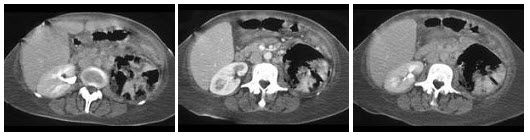

女性,65岁。畏寒、发热(40℃)伴腰痛、尿频、尿急、尿痛1周。1天来出现意识淡漠,四肢厥冷,尿量正常,血压75/45mmHg,尿沉渣可见白细胞管型及成堆脓细胞。根据病史、临床表现及体征,其诊断可能为()